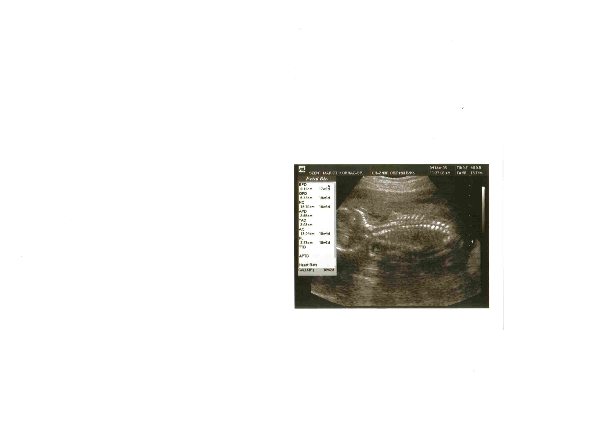

Megjöttem UH-ról, mindent rendben találtak. :D Nem lehetett végignézni sajnos a vizsgálatot, mert a falon lévő monitor bekrepált, így csak részleteiben láttam (illetve amikor méricskélték, akkor nem is, mert akkor feküdnöm kellett) :cry:

Amikor viszont felkönyökölve nézhettem, a kis pindurkánk eléggé rúgkapált, meg hadonászott a kezeivel, de ezen kívül nyugisan feküdt. Szépen látszottak a kezei, lábacskái, gerince, feje. A szonográfus mindent lemért rajta, és még mindig pontosak vagyunk méretben, azaz pont a számolt kornak megfelelő. Vagyis azt mondták, hogy ezen túl már nem is szokták változtatni a kiírás időpontját, hiába nő más ütemben később a babó. SZóval nekünk marad az aug. 3.

Próbáltuk a nemét is megnézni, még egyenlőre mindig lánykának néz ki, vagyis a hölgy nem látott fütyit. De azt mondta, hogy azért még rejtegetheti. Vagyis egyenlőre alulról láttuk, és biztosra csak akkor mondaná, ha a babó beterpesztett volna, és teljesen a lábikája közé tudtunk volna nézni. De egyenlőre marad a kislány verzió :lol:

A vizsgálatnál úgy volt bent a babó a pocimban, hogy a feneke lefelé volt, vagyis mintha ülne odabent :)

Valószínű, hogy vmikor elmegyünk 1-2 héten belül 4D-s UH-ra is, mozizni egy kicsit. Apa is nagyon kíváncsi már rá, és úgy én is meg tudnám nézni. LEhet, hogy így mégis csak 2x fogunk mozizni. A másodikat majd a 30.hét körül...

Próbálom majd berakni a képet. Azt hiszem eléggé "heringes" fotót kaptunk, ahogy apa mondaná :lol:

Megpróbálom berakni a képet, amit kaptam:

Kép

Nagyon picike lett a kép, de azért látszik. Azt hiszem ez vmi hátsó-odalsó felvétel Kismaszatról, a lábai-kezei így ki vannak takarva.

Hát tényleg olyan kis heringes, csak van rajta egy nagy fej :lol:

panna1